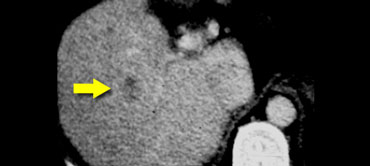

Small HCC seen only in arterial phase in a patient with cirrhosis. Small HCC seen only in arterial phase in a patient with cirrhosis.

Early appearance of HCC

It is important to separate the early appearance from the late appearance of HCC.

Nowadays we encounter very small HCC's in patients, that we screen for HCC (figure).

These are small lesions that transiently enhance homogeneously.

You will only see them in the arterial phase.

Sometimes there is rim enhancement and you might mistake them for a hemangioma.

Always look how they present in the other phases and compare with the bloodpool and remember that rim enhancement is never hemangioma.

These early HCC's are very different from the large ones that we see in the non-cirrhotic patients.